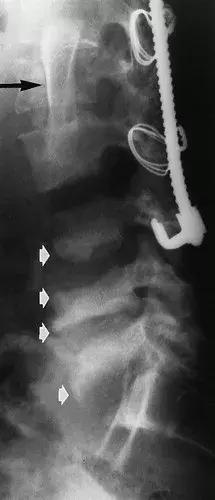

图7:侧位X线片显示一名36岁男性截瘫患者的神经性脊柱,其中有部分椎体切除术和支撑移植物(黑色箭头),和后脊柱棒治疗的L1爆裂性骨折的病史。 可以看到L3-4,L4-5和L5-S1(白色箭头)处的终板的破坏。 L3至L5椎体的密度增加有利于神经性骨关节病的诊断。